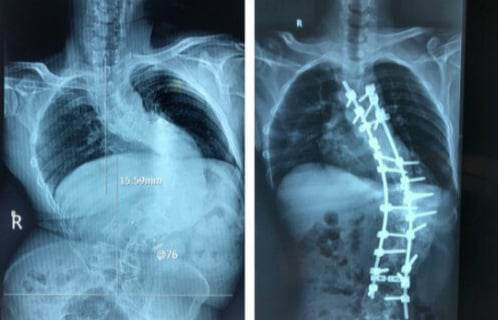

Tại Bệnh viện 108, qua các hình ảnh Xquang, tình trạng thực tế của bệnh nhân, các bác sỹ xác định đây là ca bệnh đặc biệt khó, góc vẹo rất lớn T6L3 khoảng 126 độ. Hơn nữa ca bệnh này càng khó khăn khi kèm theo gù lớn (> 100 độ).

Các bác sĩ quyết tâm phẫu thuật cho bệnh nhân với 2 thì mổ. Thì thứ nhất đi lối trước, cắt xương sườn, vén phổi, cắt tối đa được 4 đĩa đệm để làm lỏng cột sống, sau đó lắp khung Halo kéo dãn trên giường nghiêng 30 độ. Trong 3 tuần, với cân nặng tăng dần đến lúc đạt mức tối đa là 50% cân nặng của bệnh nhân. Thì thứ 2, đi lối sau, bắt vít nắn chỉnh vẹo.

Vì ca bệnh gù rất lớn nên TS.BS Phan Trọng Hậu - Chủ nhiệm khoa Chấn thương Chỉnh hình cột sống cũng là bác sĩ trực tiếp mổ cho anh A quyết định cắt V xương ở 3 mức để nắn chỉnh.

Sau mổ, hình thể người bệnh đã gần như bình thường, chiều cao tăng thêm vài cm. Bệnh nhân cảm thấy thở dễ hơn, đi lại cũng ổn hơn, và quan trọng nhất là đã tự tin hơn rất nhiều trong cuộc sống.